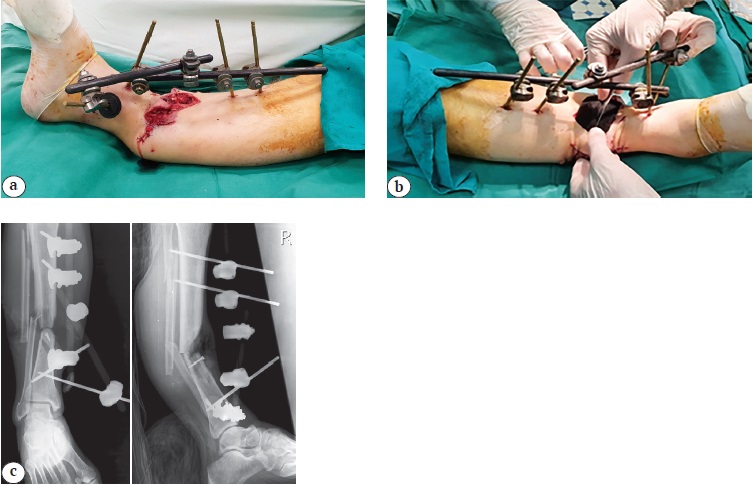

Местный статус пациента при поступлении: правая голень фиксирована аппаратом внешней фиксации КСВП, аппарат стабилен, признаков воспаления кожных покровов вокруг стержней не выявлено. Подошвенное сгибание в правом голеностопном суставе ограничено, тыльное разгибание отсутствует. На передней поверхности правой голени в средней трети визуализируется рвано-ушибленная рана размерами 17×14 см с незначительным серозно-геморрагическим отделяемым, дном раны являются поврежденные малоберцовые мышцы, мышцы разгибателей стопы и большеберцовая кость. Посередине раны имеется участок сохраненной кожи шириной 2 см. Отсутствует пульсация артерии тыла стопы, пульсация задней большеберцовой артерии определяется отчетливо. Признаков ишемии стопы нет (рис. 1).

Рис. 1. Внешний вид (а) и рентгенограммы правой голени в прямой и боковой проекциях (b) раненого при поступлении в клинику: огнестрельные переломы большеберцовой и малоберцовой костей, фиксация аппаратом КСВП (по два стержня в каждом отломке)

Figure 1. View (a) and X-rays of the patient’s right lower leg in frontal and lateral projections (b) upon admission to the clinic: gunshot fractures of the tibia and fibula, fixation with the MFRK device (2 rods in each fragment)

После обследования и лечения в клинике через 3 дня выполнена операция: повторная ПХО раны голени, в ходе которой удалены нежизнеспособные фрагменты берцовых костей. Один из костных осколков, который не потерял связи с мягкими тканями, фиксирован винтом к дистальному отломку большеберцовой кости. С целью уменьшения размеров раны выполнены острое укорочение и ангуляция голени. Преднамеренная угловая деформация голени составила 24º, укорочение — до 8 см. В ходе укорочения определяли адекватность кровотока в дистальных отделах конечности с использованием доплерографии и пульсоксиметра. На оставшиеся раневые дефекты наложена система вакуумного дренирования (рис. 2).

Рис. 2. Вид и рентгенограммы правой голени после повторной ПХО: а — голень фиксирована аппаратом КСВП на 4 стержнях в положении укорочения и преднамеренной рекурвации, размер раны уменьшился; b — в рану уложена полиуретановая губка; c — рентгенограммы голени в прямой и боковой проекциях, угол рекурвации составил 24º

Figure 2. View and X-rays of the right lower leg after repeated debridement: a — the lower leg is fixed using the MFRK device with 4 rods in the position of shortening and deliberate recurvation, the wound size has decreased; b — a polyurethane sponge is placed in the wound; c — X-rays of the lower leg in frontal and lateral projections, the recurvation angle was 24º